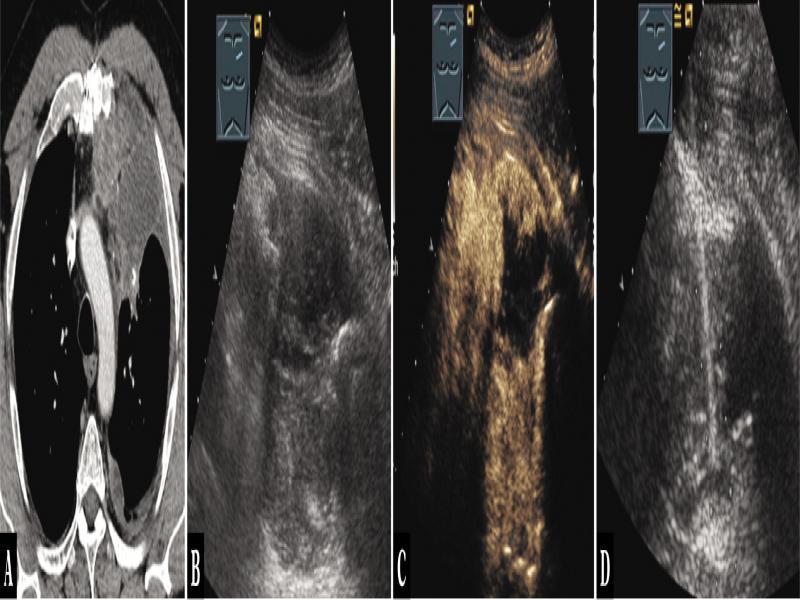

Fig. 12.

A 52-year-old male patient with thoracic pressure sensation and mediastinal tumor in the anterior mediastinum on computed tomography (A). An osteosarcoma was known from the medical history. Thoracic ultrasound indicated an inhomogeneous hypoechoic tumor (B), which showed mixed central absent enhancement on contrast-enhanced ultrasound (C). Ultrasound-guided biopsy was performed, and the diagnosis of a mediastinal sarcoma metastasis was histologically confirmed (D)